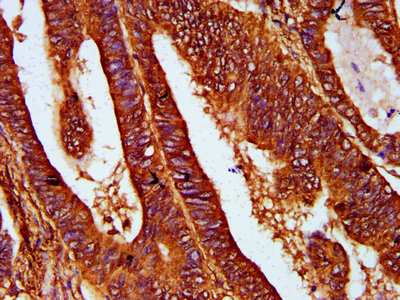

IHC image of CSB-PA887169LA01HU diluted at 1:400 and staining in paraffin-embedded human colon cancer performed on a Leica BondTM system. After dewaxing and hydration, antigen retrieval was mediated by high pressure in a citrate buffer (pH 6.0). Section was blocked with 10% normal goat serum 30min at RT. Then primary antibody (1% BSA) was incubated at 4°C overnight. The primary is detected by a biotinylated secondary antibody and visualized using an HRP conjugated SP system.